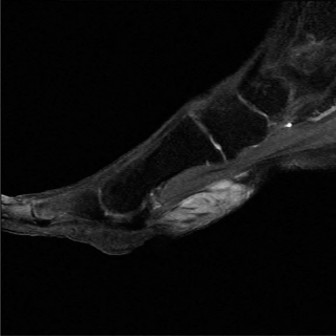

• Magnetic Resonance Imaging (MRI): The gold standard for soft tissue evaluation.

• Precisely characterizes masses (cystic vs. solid, vascularity).

• Assesses PTT integrity (tendinosis, partial tears, full ruptures).

• Evaluates inflammatory changes (bone marrow edema, tenosynovitis).

• Defines relationship of mass to neurovascular structures.

• Image (This image, potentially an MRI, could illustrate PTT pathology or an accessory navicular.)